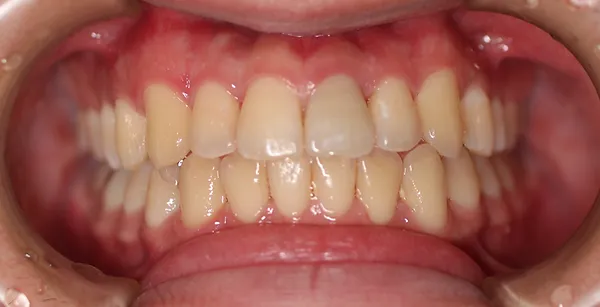

1矯正・マウスピース【治療例1】

1矯正・マウスピース【治療例2】

治療前

治療後